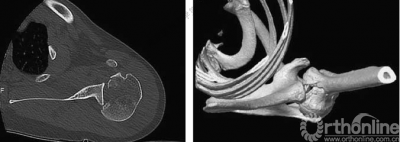

2.肩关节CT

确定肩关节后脱位。

了解反Hill-sachs损伤和程度。

观察肱骨近端主要骨折线和次要骨折线及形态。

四、分型

肩关节后脱位:

Ⅰ型: +肱骨颈骨折。

Ⅱ型: +肱骨颈骨折+小结节骨折(病例3)。

Ⅲ型: +肱骨颈骨折+小结节骨折+大结节骨折(病例2),以骨折线向肱骨近端外侧壁延伸为另一特征。

五、反Hill-Sachs 损伤对肩关节稳定性的影响

1.反Hill-Sachs损伤范围对肩关节后方稳定性具有决定性的影响。

2.常规的影像学测量方法不能准确反映损伤范围。